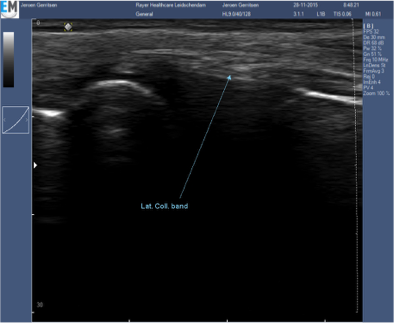

Echografie bij knie artrose

Rayer Healthcare beschikt over high-end echografie apparatuur. De fysiotherapeut is hiermee in staat om naast een uitgebreid fysiotherapeutisch onderzoek een echografisch onderzoek te doen. Met gebruik van echografie kan uw fysiotherapeut vast te stellen of er sprake is van veranderingen in het gewricht.

Tijdens de echografie zullen opnames gemaakt worden van de achterzijde van het gewricht, de binnenkant, buitenkant en voorzijde.

Gebruik van echografie op de achterzijde van de knie stelt de fysiotherapeut in staat een uitspraak te doen over de dikte van het kraakbeen dat zich bevind op de condylen in het kniegewricht. Een opname aan de binnenzijde kan verteld de therapeut of er sprake is van een botuitstulping of osteofyten. De opname aan de buitenzijde van de knie geeft informatie of er vocht in het gewricht zit wat het gewricht kapsel naar buiten kan drukken. Wanneer alle 3 de opnamen wijzen op veranderingen ten opzichte van het “normaal beeld” kan aangenomen worden dat behandeling geïndiceerd is.